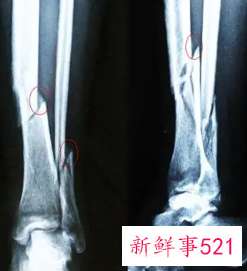

伤筋与骨折鉴别

伤筋与骨折鉴别 伤筋与骨折鉴别,伤筋动骨一百天,都是很严重的事情,伤筋和骨折鉴别,伤筋实际上就是我们常说的韧带损伤、软组织损伤,骨头还没有表...